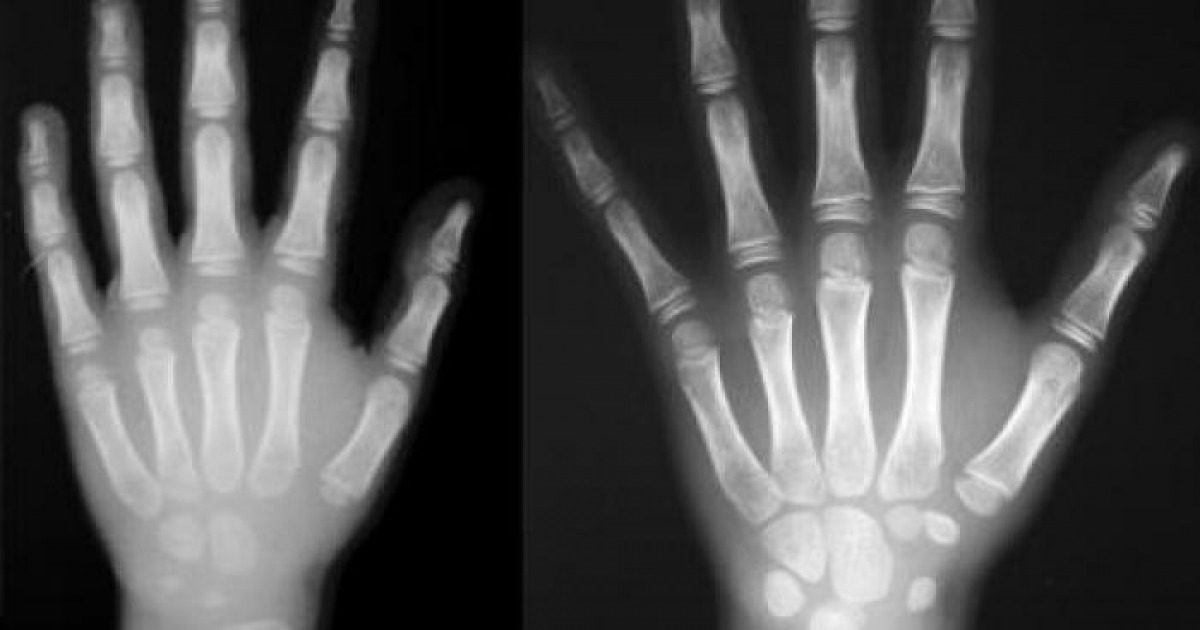

VOLEVA FARE IL FURBO. Si faceva passare per minorenne approfittando dell'aspetto giovanile e, per dimostrarlo, aveva presentato documenti d'identita' falsi. Ma i Carabinieri non gli hanno creduto e l'hanno sottoposto, in ospedale a Sant'Omero, alla radiografia del polso per stabilire l'eta' esatta.

IL FATTO. E' risultato che il bengalese, in realta', ha 18 anni. Per questo e' stato denunciato per false dichiarazioni personali e uso di documenti falsi, Il giovane ambulante e' stato fermato durante un controllo interforze contro il commercio abusivo sul litorale di Martinsicuro. Complessivamente, durante il blitz in spiaggia, sono state elevate 10 sanzioni amministrative per commercio abusivo su area demaniale per 40mila euro ed e' stata sequestrata merce per 7mila euro.